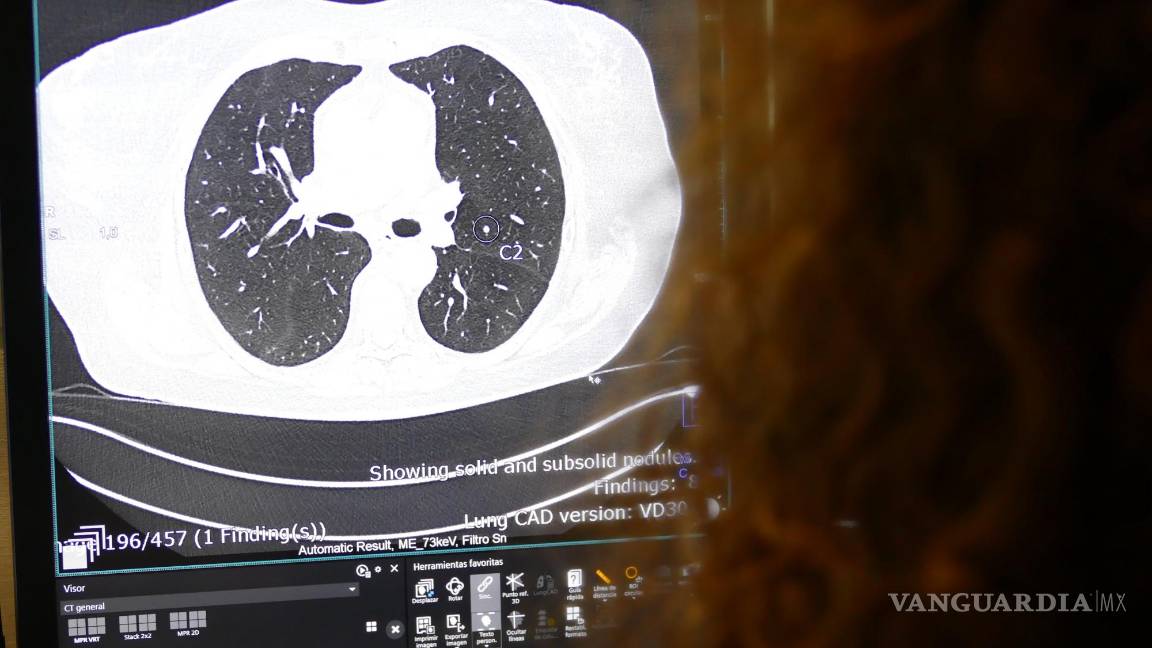

$!Imagen de una tomografía computarizada pulmonar en la que la IA muestra la presencia de un nódulo pulmonar sospechoso.

Este especialista también destaca las herramientas de IA utilizadas en las nuevas tecnologías de Diagnóstico por la Imagen, como la tomografía computarizada Photon Counting, que “posibilitan efectuar análisis instantáneos de presencia de nódulos pulmonares o derrames cerebrales”.

Este escáner detecta automáticamente los nódulos pulmonares. Si observa su presencia envía la prueba marcada al radiólogo que debe confirmar su presencia. Lo mismo hace con las tomografías computarizadas cerebrales; si detecta una hemorragia, alerta a los especialistas”, señala Martínez de Vega.

Hasta hace no mucho tiempo un escáner de tórax estaba compuesto por 50 imágenes. Ahora tiene 1,200. Ningún radiólogo puede analizar tantas imágenes. Necesitamos que la IA nos ayude. Además, hay lesiones que el ojo humano no ve y que la IA detecta”, explica.